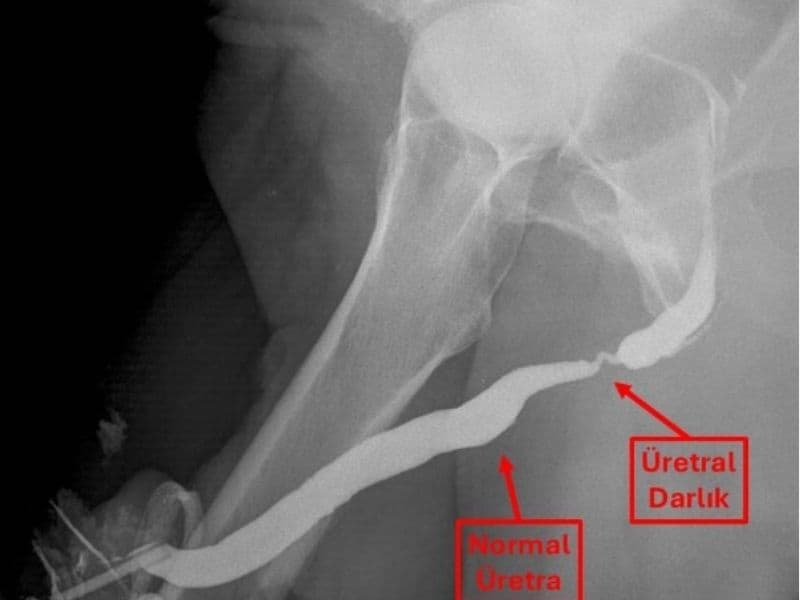

- Üretra filmi (üretrografi) (Penis ucundan özel ilaç verilerek çekilen röntgen filmi)

- Endoskopik inceleme (sistoskopi/üretroskopi) (kamera ile idrar yoluna bakılır)